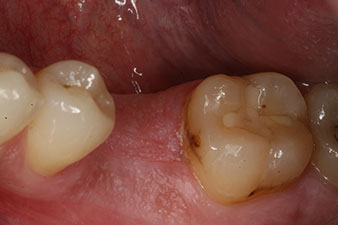

L’extraction d’une première molaire mandibulaire, comportant d'importantes lésions cariées, accompagnées de complications endodontiques, devait être pratiquée chez un jeune patient. L’implant était la seule alternative à la pose d’un bridge s’appuyant sur les dents voisines globalement saines. Six semaines après l’extraction, l’alvéole présentait une insuffisance osseuse. L’implantation a dû être associée à une augmentation osseuse.

Un patient de 28 ans ayant des antécédents de tabagisme important a dû se faire extraire la dent 36 à la suite d’une parodontite apicale récidivante.